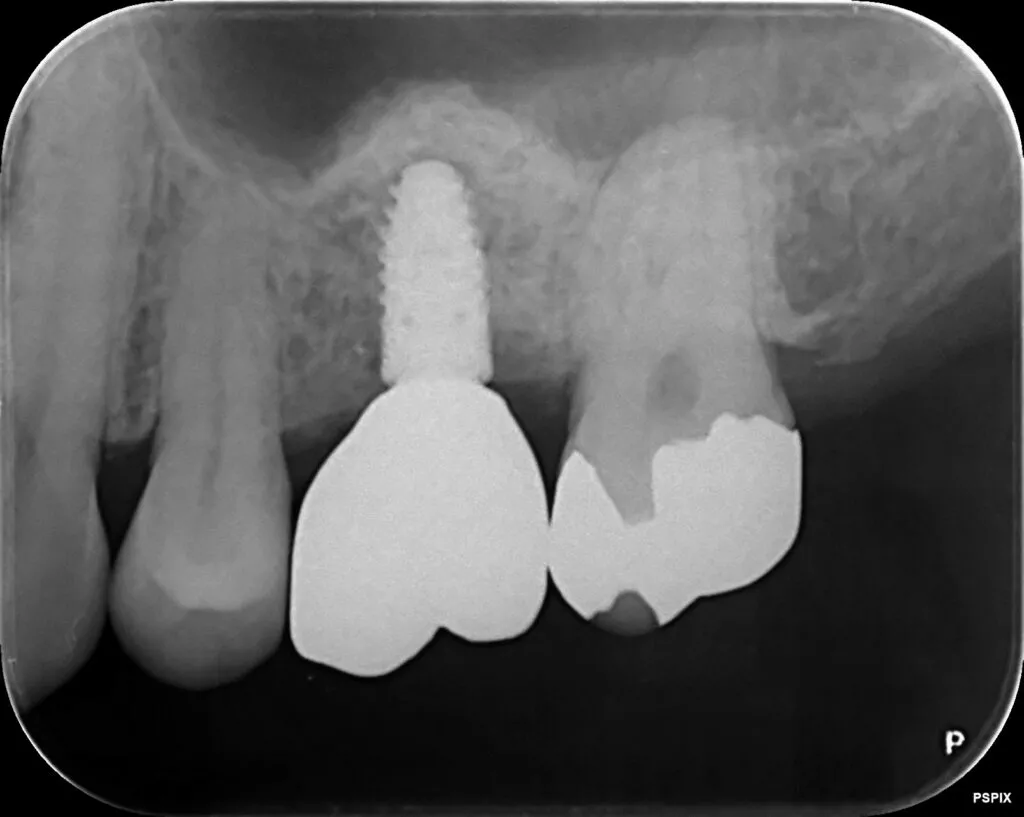

インプラント治療症例①

インプラント治療症例②

インプラント治療症例③

インプラント治療症例④

インプラント治療症例⑤

インプラント治療症例⑥

歯周病などで骨が少なくなった患者さんに対して行う、骨を再生させる処置(ソケットプリザベーション)